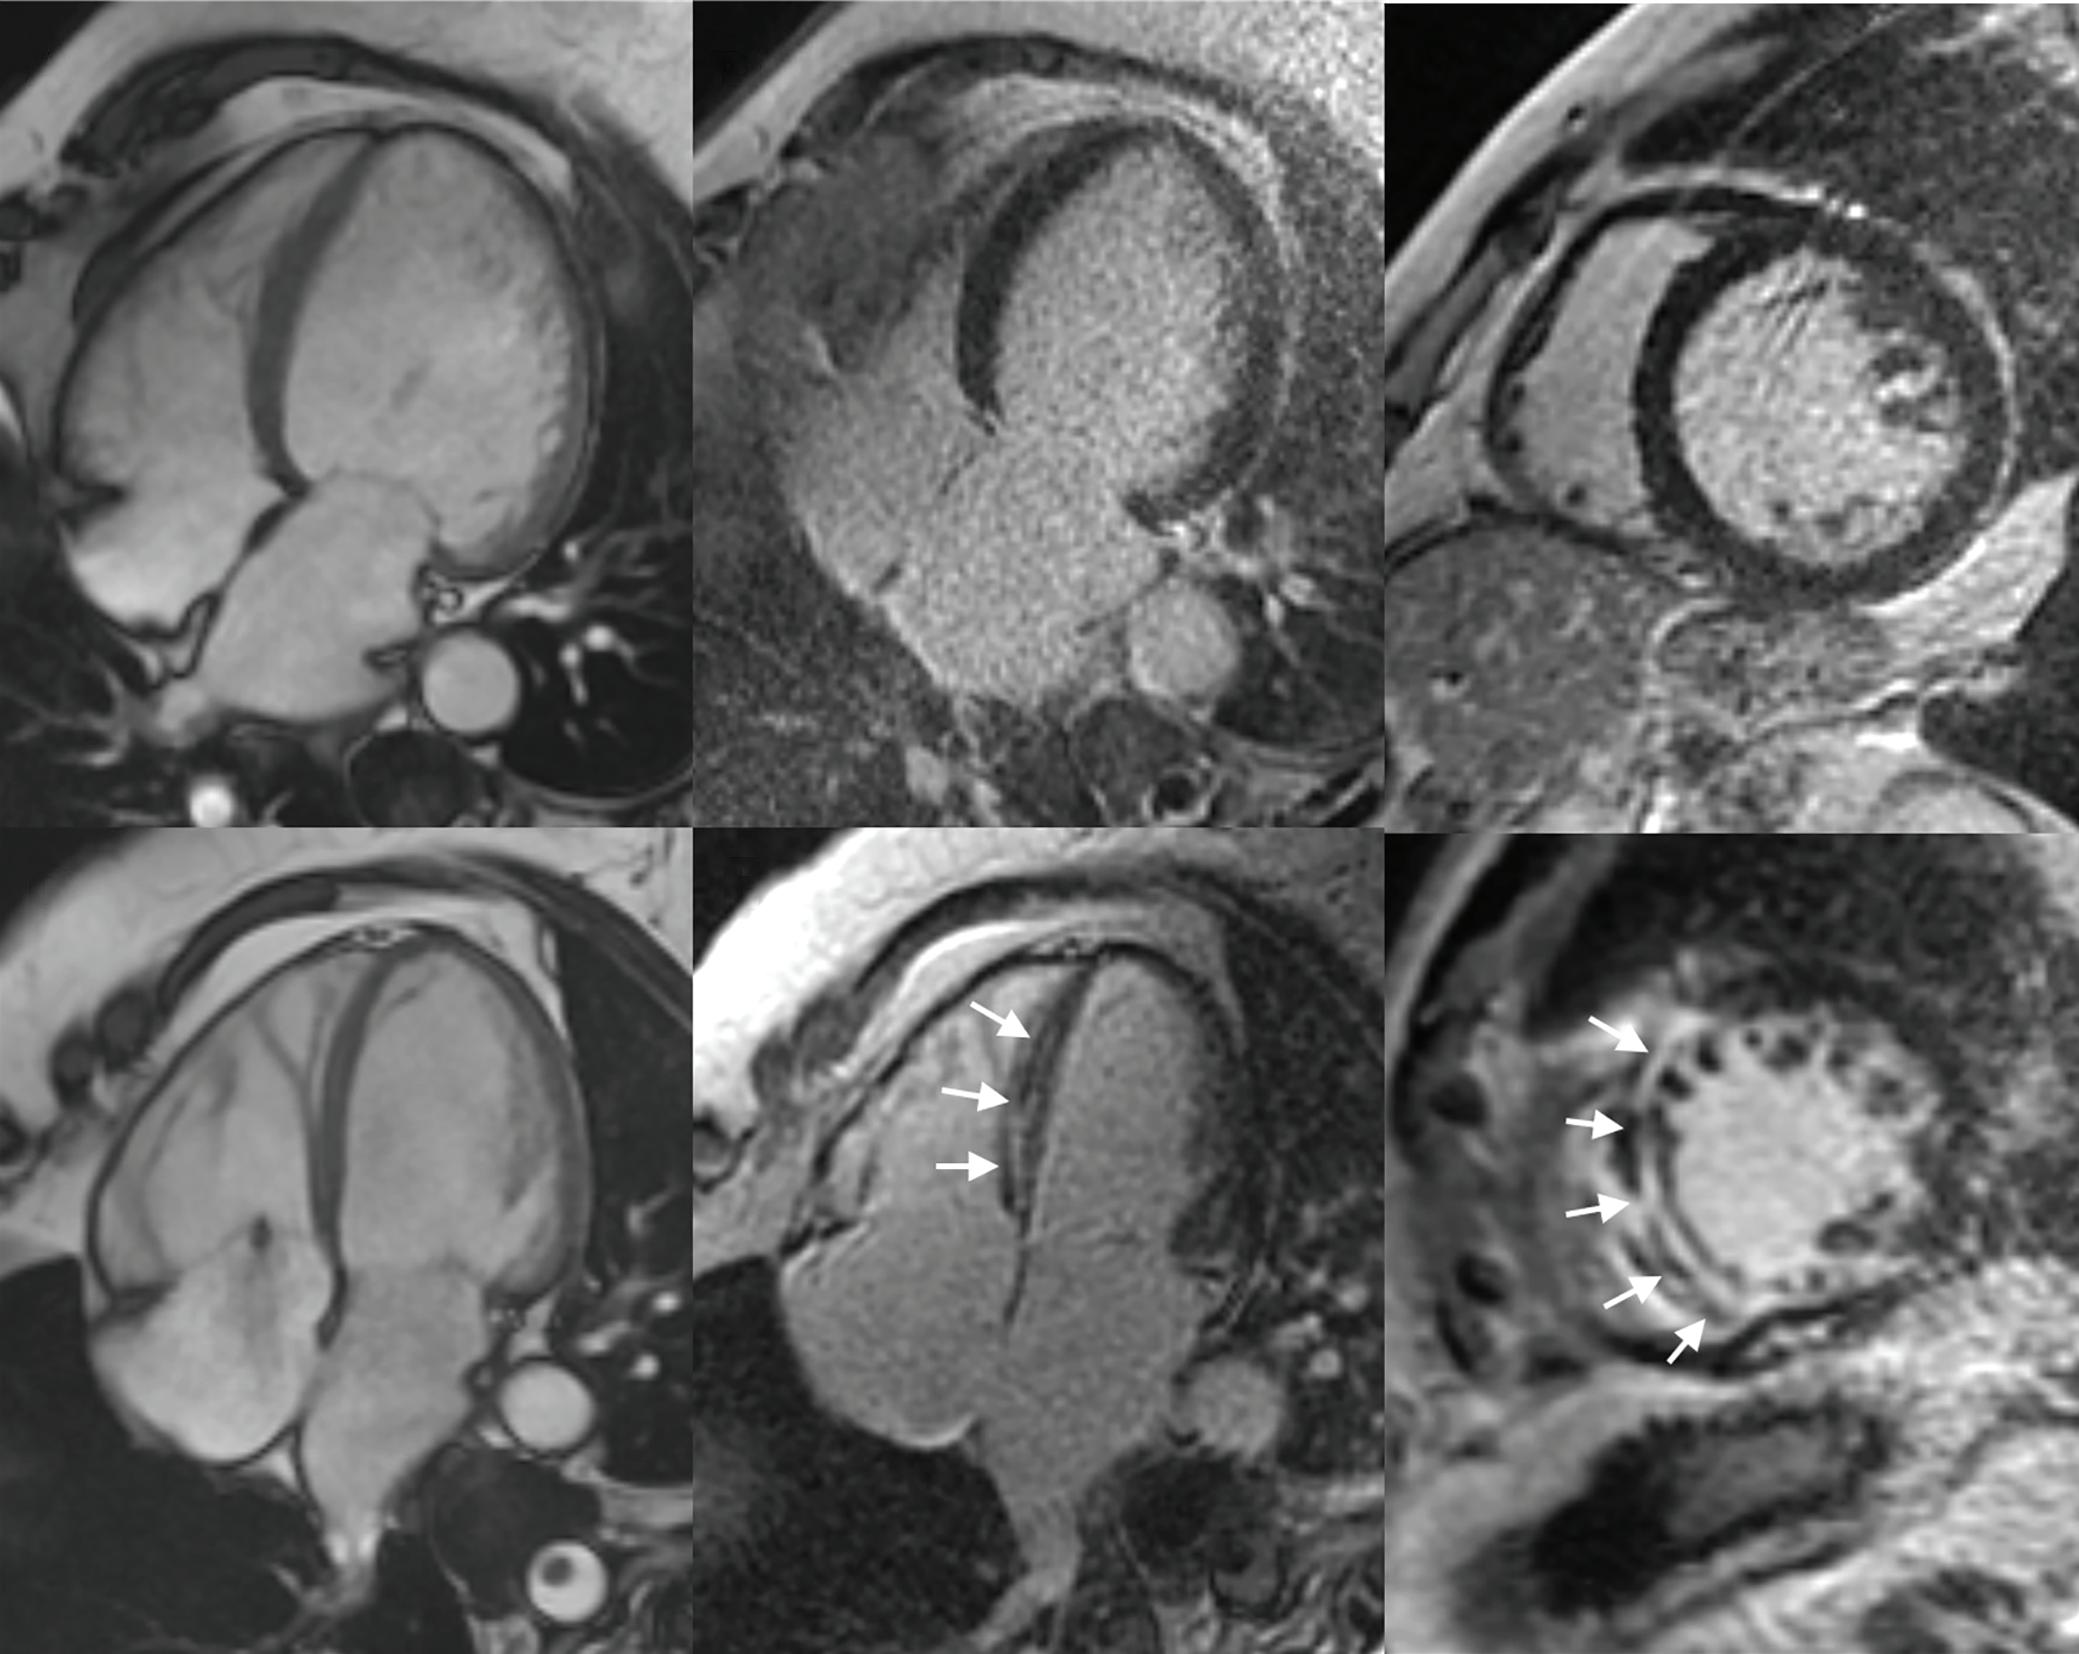

Role of Imaging in Cardiomyopathies

Vincenzo Castiglione, Alberto Aimo, Giancarlo Todiere, Andrea Barison, Iacopo Fabiani, Giorgia Panichella, Dario Genovesi, Lucrezia Bonino Alberto Clemente, Filippo Cademartiri, Alberto Giannoni, Claudio Passino, Michele Emdin and Giuseppe Vergaro

DOI: https://doi.org/10.15420/cfr.2022.26